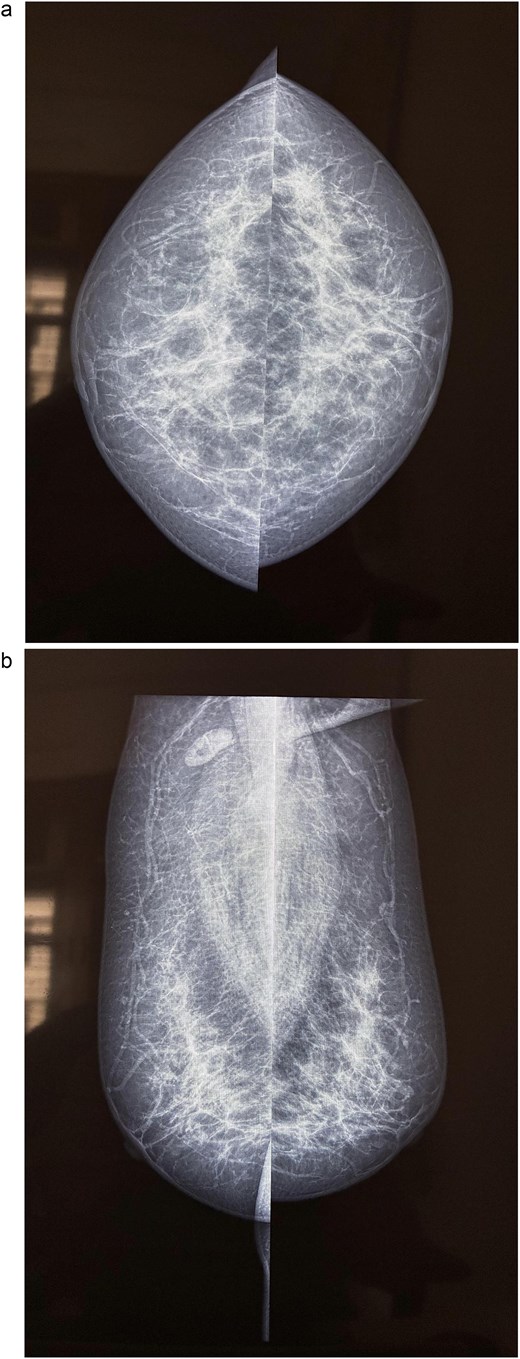

A 58-year-old woman with no relevant family history underwent routine health screening during which a left breast lump was detected. Mammography showed a high density spiculated lesion in the upper outer quadrant (BIRADS 4c/5) (Fig. 1a and b). Ultrasound demonstrated a 1.0 × 1.1 cm spiculated, heterogeneous hypoechoic lesion (BIRADS 4c). FDG positron emission tomography computed tomography (PET CT) revealed mild uptake confined to the breast lesion (SUVmax ~2.5) with no FDG avid axillary nodes or distant disease (Fig. 2a and b). Ultrasound guided FNAC revealed infiltrating ductal carcinoma (Yokohama Category 5) with cohesive clusters and scattered malignant ductal epithelial cells showing nuclear overlapping, moderate pleomorphism, conspicuous nucleoli, and moderate cytoplasm in a hemorrhagic background.

FDG PET CT images of the chest. (a) Axial PET CT image showing a well-defined FDG avid lesion in the upper outer quadrant of the left breast , consistent with the known carcinoma, with no evidence of axillary or mediastinal lymphadenopathy. (b) Coronal PET CT image demonstrating the left breast lesion in the upper outer quadrant without invasion into the chest wall or adjacent structures, consistent with localized disease.